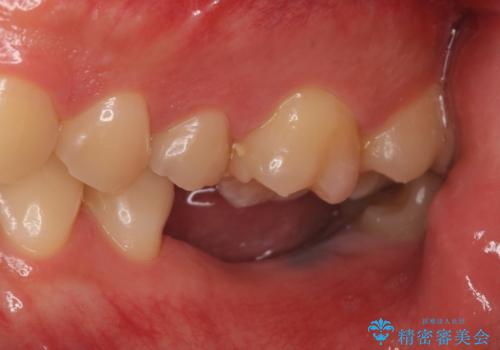

- 数年前に左下の奥歯を2本失ってから物が咬めないため何とかして欲しいと当院にいらっしゃった方の症例です。

左下にインプラント(ストローマン)を2本埋入し、オールセラミッククラウンによる補綴を行いました。